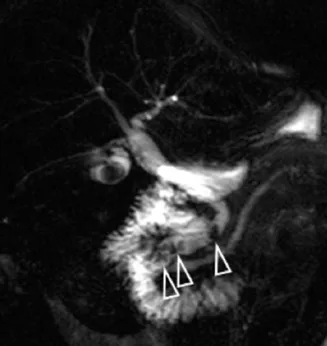

Figure 1. Patient exploré par bili-IRM pour une suspicion de migration lithiasique.

A. Cette coupe de bili-IRM 2D montre de multiples lithiases vésiculaires, ainsi qu’un calcul du bas cholédoque (tête de flèche).

B. Sur cette projection cholangiographique « MIP » issue d’une acquisition 3D en coupes fines, le calcul cholédocien est trop

petit au sein de cette VBP dilatée, et il n’est pas correctement visualisé. En cas de bili-IRM 3D, l’analyse de chacune des coupes

fines du volume est impérative. Ainsi, contrairement à la projection « MIP », la coupe fine passant par le cholédoque permet

de bien montrer le calcul (C)